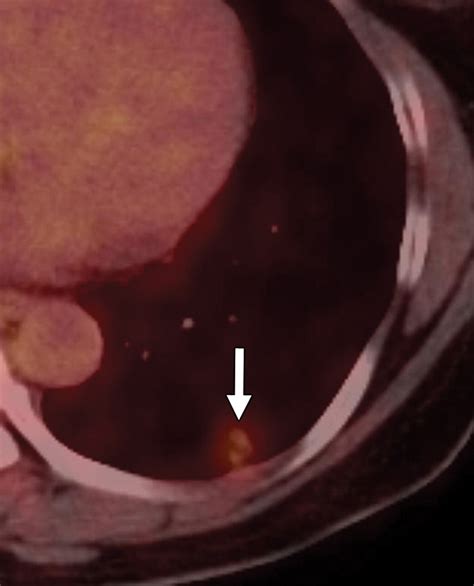

While the majority of these nodules are benign or very slow-growing, there are specific "red flags" that may prompt a more aggressive diagnostic approach. If a ground glass nodule begins to develop a larger solid component, or if it shows a rapid increase in size over a short timeframe, your medical team may transition from surveillance to diagnostic testing. This could involve a PET scan to check for metabolic activity or a biopsy to extract a tissue sample for laboratory analysis.

Modern medicine has significantly improved the prognosis for early-detected lung abnormalities. Through the use of low-dose CT screening, many early-stage growths are identified when they are still highly curable. The key is consistency in your follow-up appointments and maintaining open communication with your healthcare provider.